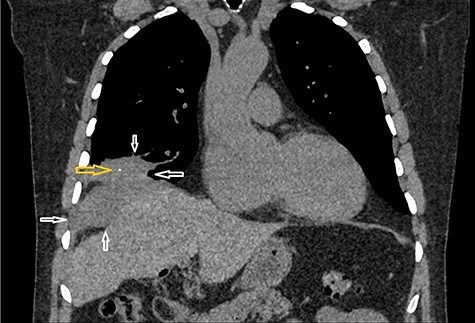

Because of previously identified calcification in the mass lesion and history of laparoscopic cholecystectomy, a non-contrast CT scan abdomen was obtained to ascertain if spilled gallstones were responsible for the recurrent abscess formation (Fig. 3).

Non-contrast CT abdomen: CT scan demonstrates a small hyper dense calculus in the abscess marked by an arrow. Here patient is lying in slightly left lateral position due to pain caused by the abscess.